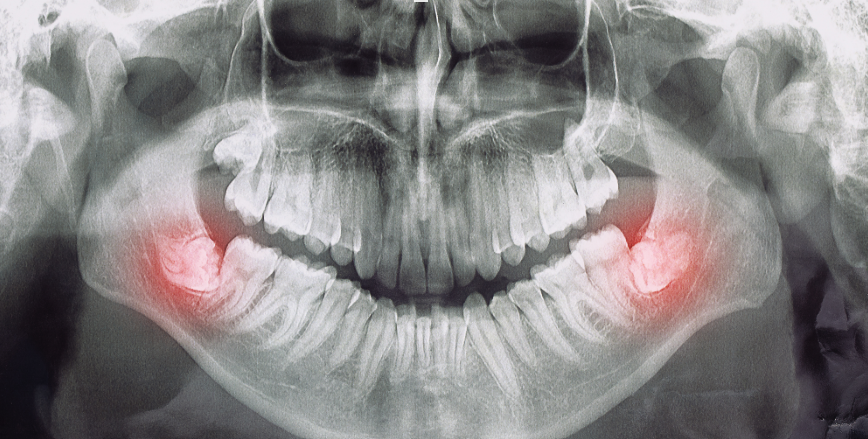

Impacted wisdom teeth can lead to the formation of cysts or other oral lesions, which may damage surrounding bone and nearby teeth. In some cases, the pressure from impacted teeth can even affect nerves, causing pain or numbness. Extracting wisdom teeth early can prevent these more serious complications and minimize the risk of long-term damage.

Dentists often recommend evaluating wisdom teeth in the late teens or early twenties, even if they aren’t causing immediate problems. Early removal can be easier and involve fewer risks, as younger patients typically heal faster and experience less postoperative discomfort. Regular dental checkups and imaging help determine the optimal timing for extraction based on each individual’s oral anatomy and needs.